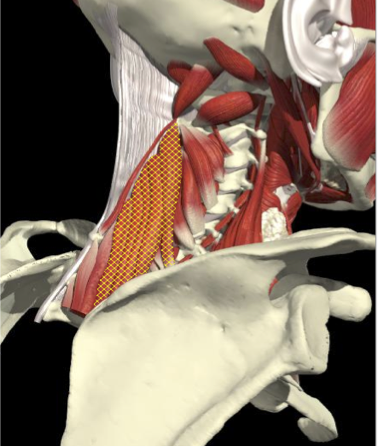

LATEROCOLLIS

Long muscles transversing spine

- Levator scapulae

- Scalenus Anterior/medius

- Semispinalis cervicis

- Longissimus cervicis

Biomechanical advantage

- Range - 37 degrees

ACCURACY OF LOCALIZATION LEVATOR SCAPULAE

LOCALIZATION OF MUSCLES IN DEEPER LAYERS